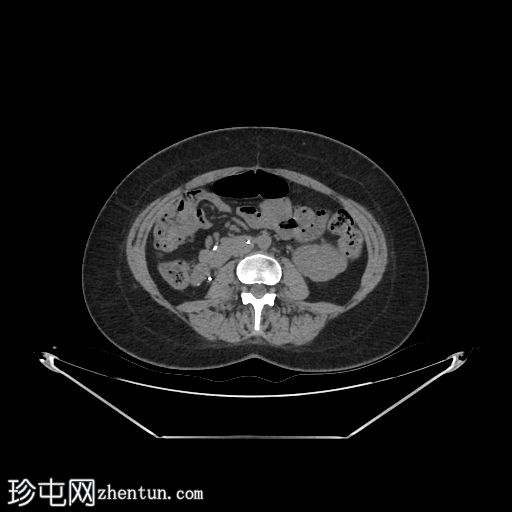

轴位

平扫

自体肾脏和胰腺(胰头、胰体和胰尾)明显萎缩。

移植的胰腺位于右侧腹膜后间隙,大小和形态(轴位、冠状位和矢状位)均正常,可见相关手术缝合线。供体十二指肠段与自体十二指肠吻合。可见胰腺移植物与右髂血管的动脉吻合,胰腺实质强化均匀,提示移植物灌注良好。

左髂窝肾移植(轴位、冠状位),显示移植肾与同侧髂总血管的动脉和静脉吻合。移植肾形态完整,实质均匀强化。

本例中,影像学检查显示原位肾脏和胰腺明显萎缩,符合长期糖尿病合并慢性肾脏病的表现。肾移植位于左髂窝,与同侧髂血管的动脉和静脉吻合通畅,肾实质均匀强化,这些影像学表现均符合功能性肾移植的影像学特征。移植胰腺位于右侧腹膜后,形态和位置均符合原位胰腺,供体十二指肠袢与原位十二指肠吻合良好。